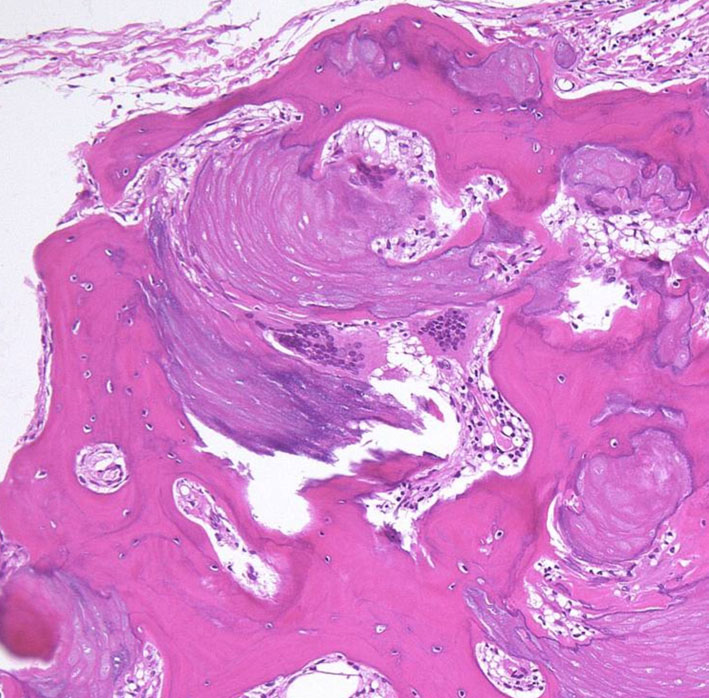

摘出した骨化片の病理像です。成熟した骨組織 mature boneです。

adamantinomatous typeです。mature boneの端には破骨巨細胞が多数見られます。

鞍内にあった部分の病理所見です。adamantinoomatous typeで,破骨細胞を伴う強い骨化がみられます。